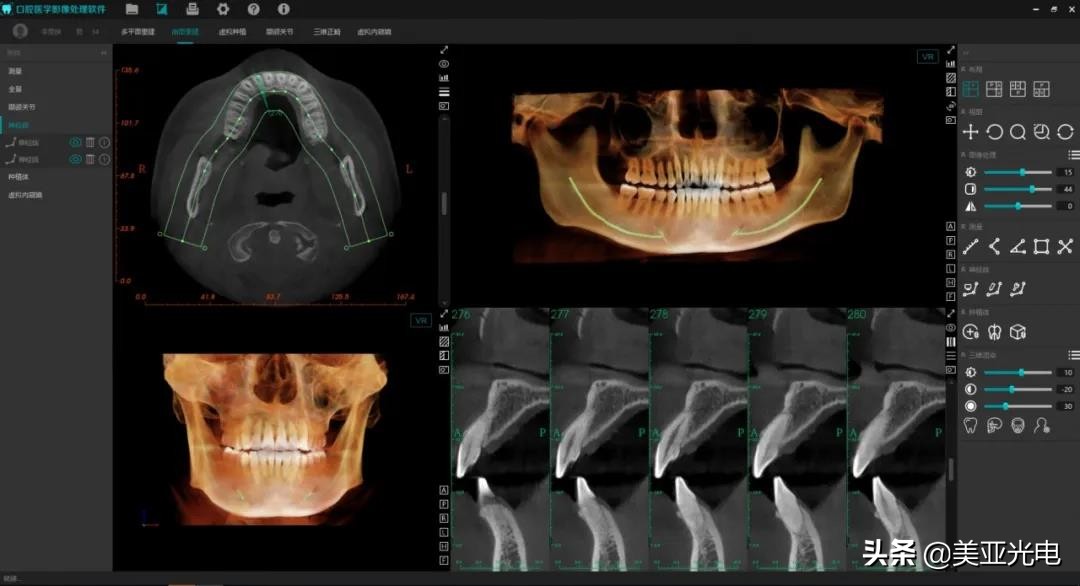

▲美亚口腔CBCT—种植

美亚智能3D诊断软件应用人工智能技术进行模块化设计,具备多平面重建、曲面断层重建、种植模式、TMJ模式、三维正畸模式等功能,可实现模拟种植、自动神经管标注、自动骨密度分析、自动定位TMJ、自动合成侧位片、三维气道分析等。

▲化繁为简,针对不同的临床应用提供了丰富便捷的工具